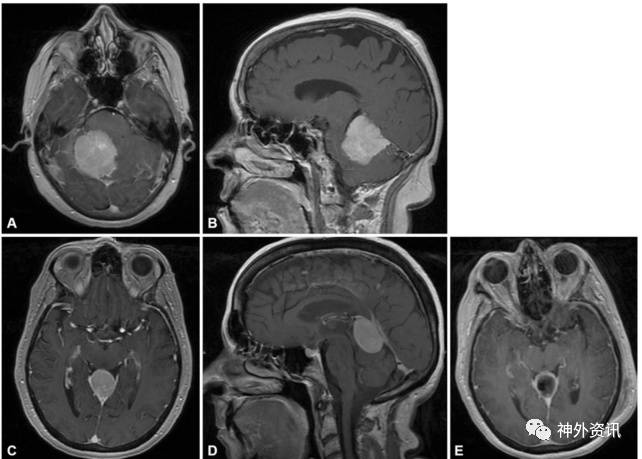

图5. 松果体区肿瘤生长模式图。肿瘤向上生长并挤压胼胝体压部是经前纵裂胼胝体压部入路的最佳适应证。大脑内静脉可被肿瘤推向上方(A)、下方(B)或侧方(C)。

图6. 1例患者术前术后MR影像及术中照片。术前MRI(A.轴位;B.矢状位;C.冠状位)提示肿瘤起源于镰幕交界区,位于大脑内静脉上方,将胼胝体压部推向前下方,呈均匀强化。D.术中在胼胝体压部上方显微分离;E.显露肿瘤;F.瘤内减压并沿肿瘤包膜分离后;G.切除肿瘤。术后MRI(H.轴位;I.矢状位;J.冠状位)提示肿瘤全切除。

图7. 1例术前MRI(A.轴位;B.矢状位)提示松果体区肿瘤向幕下生长,胼胝体压部未受压移位。该病例采取顶枕开颅后纵裂入路。另1病例,术前MRI(C.轴位;D.矢状位)提示松果体区肿瘤完全位于幕下,采用幕下小脑上入路切除肿瘤;E为术后影像。